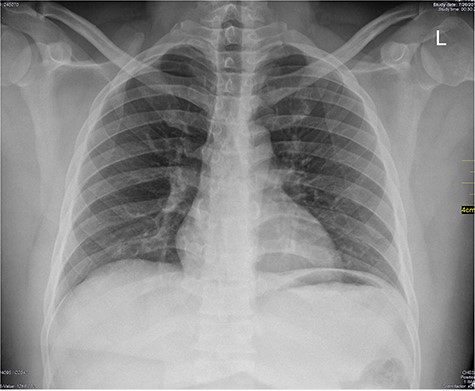

Chest X-ray was normal as shown in Fig. 1. Focused abdominal sonography for trauma (FAST) scan showed mild left perihepatic collection necessitating a thoracoabdominal computerized tomography (CT)-scan which showed external oblique muscle laceration with intermuscular air lucencies and grade 2 hepatic injury as shown in Figs 2–4. Other blood work-up were normal. No other injury was found on secondary survey. His wound was explored under local anaesthesia, primarily repaired, and he was discharged after 24 h of close observation.

Showing lucent air densities tracking through the right intercostal muscles and abutting on the liver in the epigastrum with associated subcapsular haematoma in the left lobe of the liver.